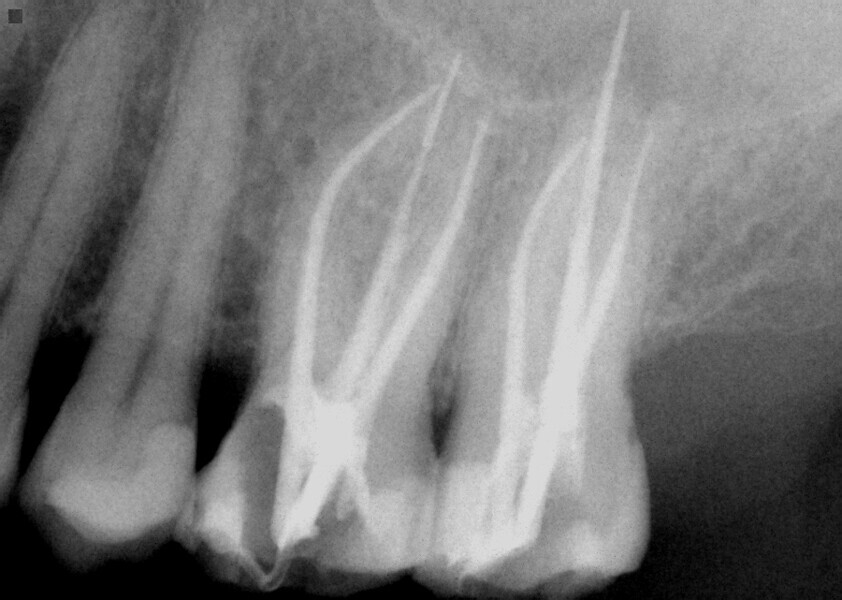

Fig. 16: Patient presented with percussion and hot sensitivity on the lower first molar that she reported was increasing over the past week.

Fig. 17: Instrumentation was performed with ExactTaperH DC files and single cone obturation with Bioceramic Root Canal sealer completing the endodontic treatment preserving the cervical tooth structure during the treatment.